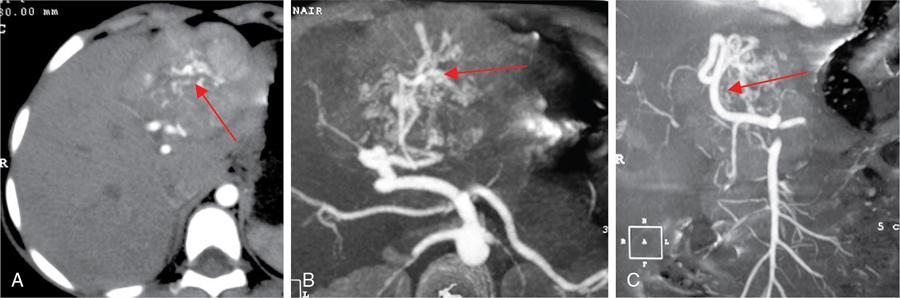

CT

MRI